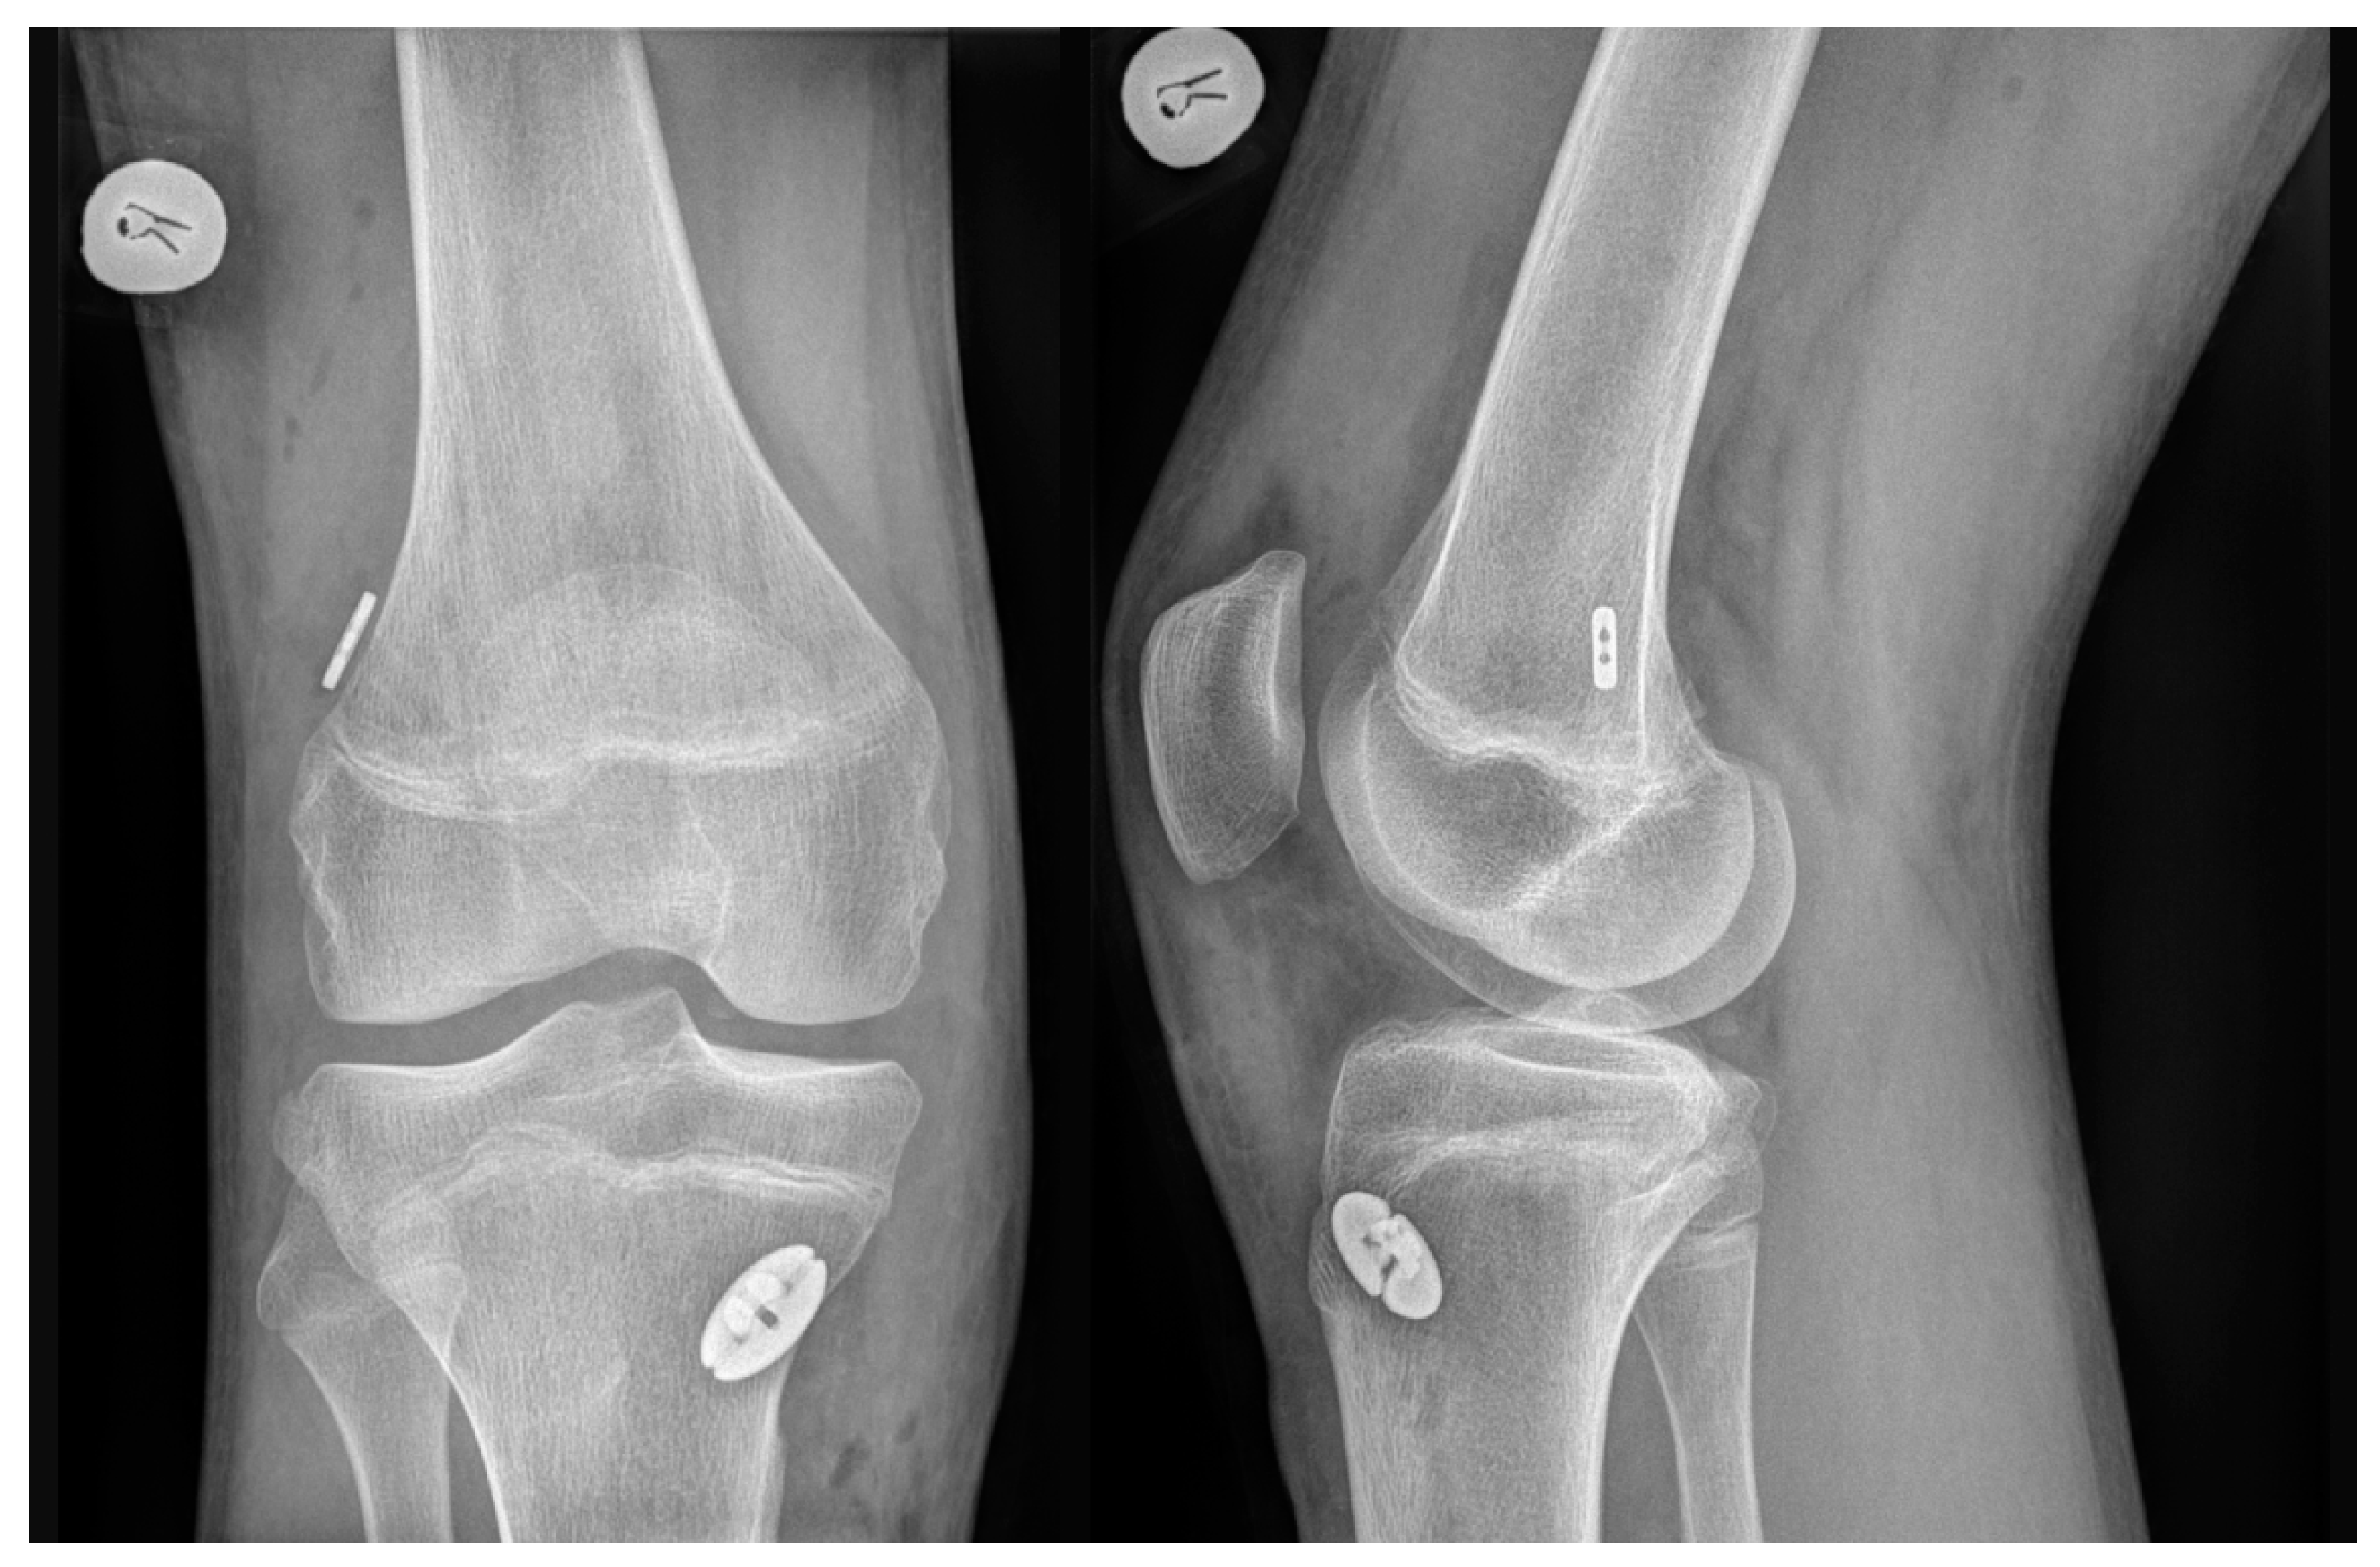

For all autografts, the same transepiphyseal tunnel drilling technique was performed. A 4 mm-diameter full femoral tunnel was drilled along with a 2-to-2.5 cm deep femoral socket, according to the graft diameter. Full tibial tunnel was drilled according to graft diameter. Both HT and QT autografts were fixed in the knee joint with cortical suspensory devices on both the femur and the tibia (TightRope RT and ABS TightRope, Arthrex (Naples, FL, USA)). A post-operative X-ray examination was performed after each ACLR to confirm the position of the implants (Figure 2).

Figure 2.

Post-operative X-ray examination confirming the position of the implants.